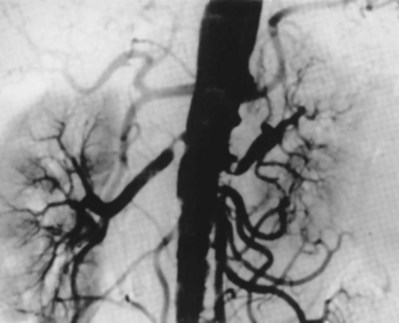

Intrarenal aneurysms are considered congenital and account for one fifth of aneurysmal disease affecting the kidney (Fig. 54–47). In some instances they may develop secondary to atherosclerosis, mural dysplasia, trauma, inflammation (arteritis), or needle biopsy. Intervention is warranted for lesions larger than 2 cm or those associated with hypertension. Lesions can rupture and dissect leading to ischemia or may contribute to thrombus formation and warrant intervention (revascularization or coil placement). Women in childbearing age with evidence of aneurysms are urged to undergo repair secondary to risk of rupture and associated high rates of maternal and fetal mortality (Figs. 54-48 and 54-49) (Yang and Hye, 1996; Centenera et al, 1998).

Figure 54–47 A, Large left congenital renal aneurysm and arteriovenous malformation. B, Note early filling of the renal vein and inferior vena cava.